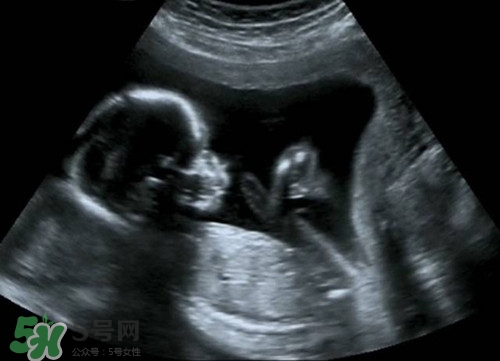

怀孕多久可以做b超?怀孕做b超对胎儿有影响吗

》的解答。1.怀孕b超对胎儿有影响吗2.怀孕做b超对胎儿有影响吗3.怀孕做b超对胎儿有影响吗4.怀孕期间做b超太频繁有没有影响1、目前临床上所应用的B超,其探头发射的声强度小于10毫瓦/平方厘米,而且超声检查的时间往往只有5~10分钟,对每个器官的探测时间更短.所以说,B超检查对胎儿的危害是极小的,不会影响胎儿的身心发育.因此,孕妇不必对孕期B超检查产生恐惧心理,适时的B超检查是确保胎儿正常发育的重要手段.正常情况下,妊娠早期应进行次B超检查,以明确是否妊娠,并确定妊娠的天数。